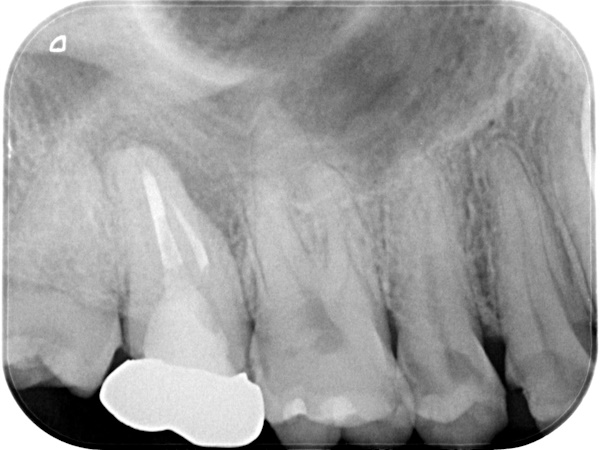

【 上の歯の精密根管治療 】

治療前と治療後の比較

初診時